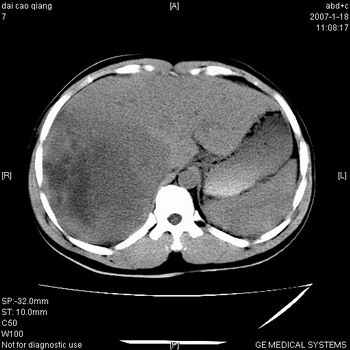

符合巨块型肝癌表现:

1、平扫低密度,增强后表现为快进快出。

2、动脉期可见迂曲的动脉供血血管

3、并可见门静脉右支癌栓形成

4、可见假包膜

5、腹主动脉旁结节影,考虑肿大淋巴结。

肝右叶巨大不均匀低密度肿块,前缘有假包膜,增强明显的呈快进快出表现,门脉右支有癌栓,病人虽然年轻但还是首先考虑肝右叶巨块形肝癌,病人血象高只能说有合并感染。不支持肝脓肿。